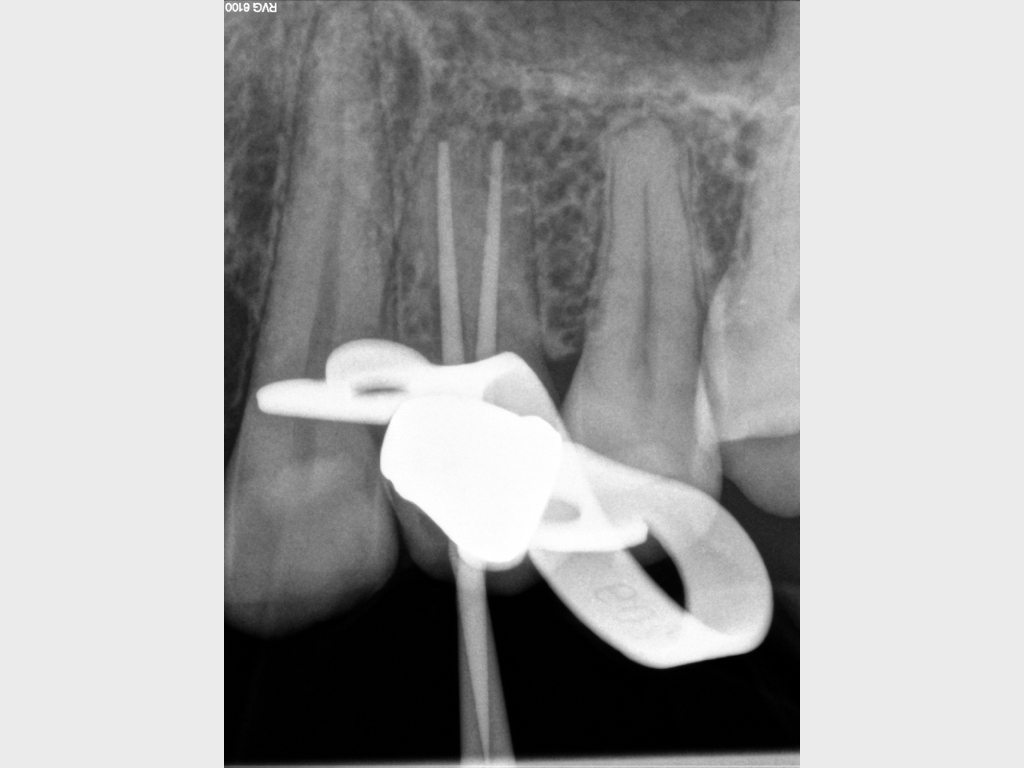

7078.004

12. Oktober 2020

Routine